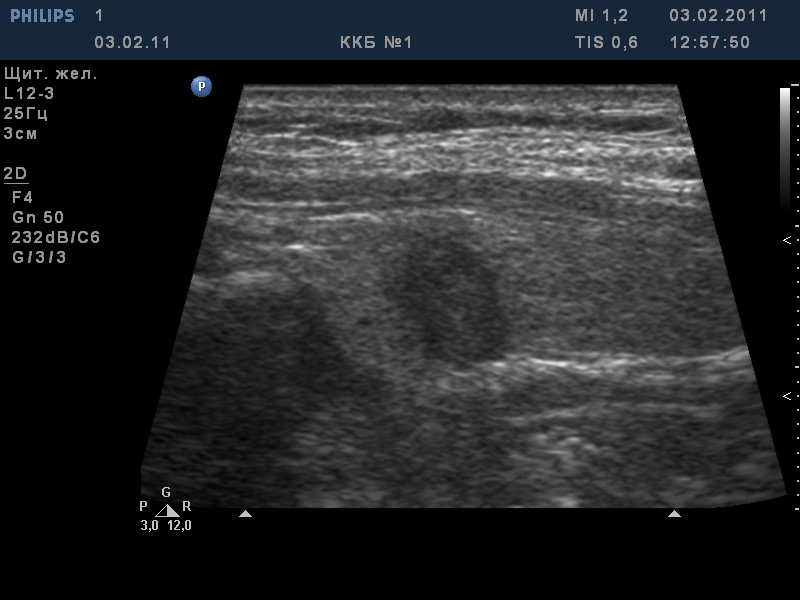

TI-RADS 4. Узлы более 1,0 см в диаметре с “малыми” признаками злокачественности для выполнения ПУНКЦИИ (рис. 3):

- солидные узлы, равномерно или неравномерно умеренно пониженной эхогенности;

- солидные узлы изо- или гиперэхогенные, имеющие “малые” признаки злокачественности:

– гипоэхогенные включения;

– округлая/шаровидная форма;

– неравномерно утолщенное хало;

– макрокальцинаты.

Рис. 3. TI-RADS 4: а – узел шаровидной формы, с ровными и четкими контурами, умеренно пониженной эхогенности, с участками более низкого эхо, с макрокальцинатом. Узел окружен тонким хало (фолликулярная неоплазия); б, в, г (поперечное и продольное сканирование левой доли ЩЖ) – изоэхогенные узлы с гипоэхогенными включениями, с четкими контурами, с тонким хало (фолликулярная аденома); д – изоэхогенный узел с гипоэхогенными включениями, с неравномерно утолщенным хало (фолликулярный рак).